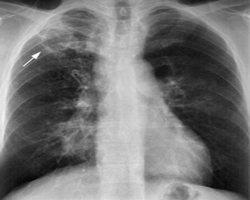

Chest and Tuberculosis (TB)

TB is caused by the bacterium Mycobacterium tuberculosis (M tuberculosis). TB is contagious. This means the bacteria is easily spread from an infected person to someone else. You can get TB by breathing in air droplets from a cough or sneeze of an infected person. The resulting lung infection is called primary TB.

TB can affect any organ system, although manifestations are most commonly related to the chest. The lungs are the most common and often the initial site of involvement. Chest involvement is most commonly pulmonary, followed by lymph nodal and pleural disease (latter two are included under EPTB). Chest wall, cardiac, breast, and skeletal involvement can also occur in the thorax.

The primary stage of TB does not cause symptoms. When symptoms of pulmonary TB occur, they can include:

• Breathing difficulty

• Chest pain

• Cough (usually with mucus)

• Coughing up blood

• Excessive sweating, especially at night

• Fatigue

• Fever

• Weight loss

• Wheezing